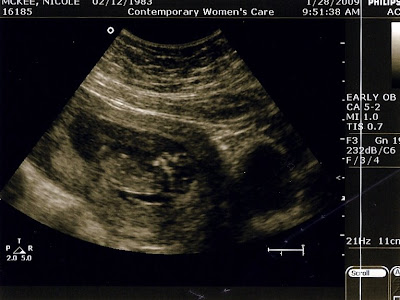

I'll leave you with some pics from our 2/10 appt:

(***IF YOU CLICK EACH PIC, IT WILL GET BIGGER***)

Profile shot. Baby was wiggling a lot again, but not as many log rolls as last time. It seems we already have a morning person on our hands. Please note the tightly closed legs. They're crossed at the ankles and kicking me. Hey, modesty is awesome.

Baby's face is turning away from the ultrasound wandy-thing in this pic. I can just hear, "LEAVE ME ALONE, PEOPLE!" Ahhhh, definitely my kid.

AND FINALLY, the same profile shot above, this time DECODED for those that don't speak ultrasound. I had no clue - with Rich as my witness, I had the u/s tech point out all the body parts. I am NOT GOOD at little wiggly blobs!